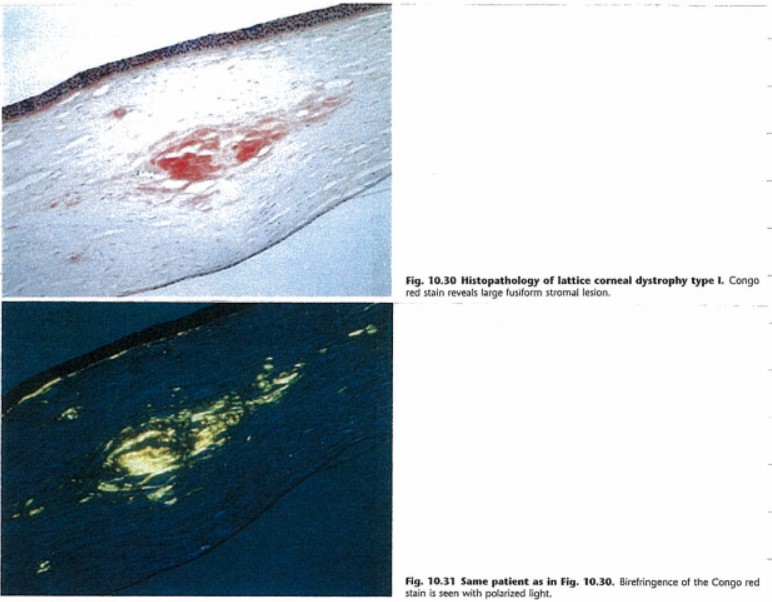

각막 표층기질 및 보우만층에 아밀로이드 물질이 침착되는데,

congo red stain 에서 특징적으로 염색됩니다.